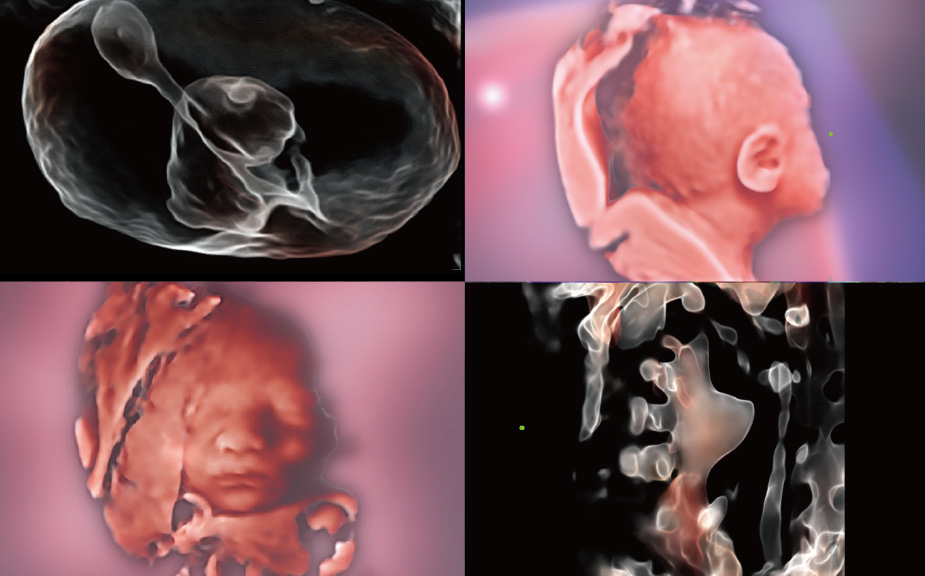

Scenario-oriented Full-stack Intelligence

The innovative Smart Scene 3D solution enables automated identification of tissue characteristics and delivers organ-specific diagnosis with full-stack intelligence throughout the entire procedure. This innovation reduces dependence on clinical skills, while elevating diagnostic accuracy, confidence, and efficiency.